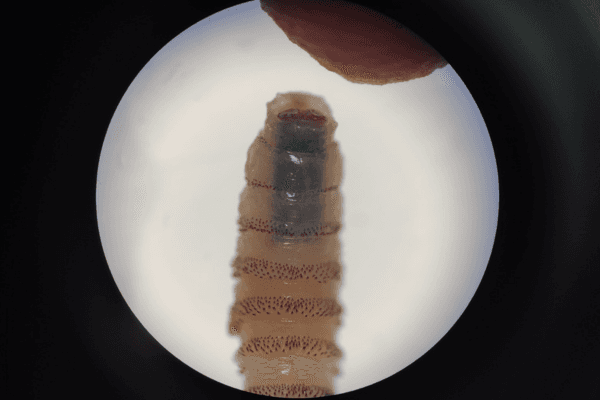

Los gusanos barrenadores son larvas de mosca que se introducen en heridas abiertas de animales de sangre caliente y se alimentan de tejido vivo, avanzando como un tornillo en la carne. Si no se tratan, las infestaciones pueden ser mortales tanto en animales como en humanos.

Hasta ahora este parásito había afectado principalmente al ganado, siendo excepcional la infestación de personas. El tratamiento médico, en estos casos, generalmente se resuelve con un tratamiento que consiste en retirar manualmente las larvas y desinfectar las heridas.